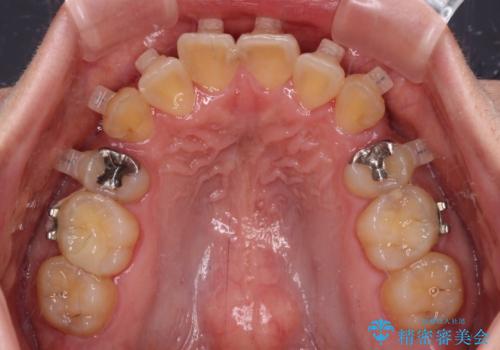

- 海外で抜歯矯正を開始し、治療途中で帰国したため、転院先を探しているとのことで来院された患者様です。

ワイヤーは抜けてしまい、後戻りが始まっている状態でしたが、既存の装置を継続利用して受け入れてくれる医院が見つからないとのことでした。

当院では、張り替える必要のある部位は張り替えることで継続することとし、抜歯スペースを閉じていくように治療を行うこととしました。